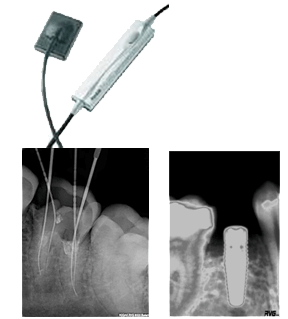

Las radiografías son necesarias antes durante e inmediatamente después del tratamiento endodóntico, y para evaluar periódicamente el éxito o fracaso de la terapia. Por lo tanto son requeridas repetidas exposiciones a las dosis de radiación. Muchos investigadores han sugerido los efectos deletéreos por radiaciones excesivas y repetitivas dentro de las cuales se encuentran: mucositis, serostomia, sialoadenitis, destrucción de la substancia del diente, necrosis de las células pulpares reabsorción radicular, retardo del desarrollo dental, inhibición de la erupción, anodoncia y osteoradionecrosis, como también anormalidades en el desarrollo del feto siendo el periodo de organogénesis el más sensitivo entre los 18 y 45 días de gestación. La RC nos da una imagen en dos dimensiones de un objeto de tres dimensiones, además para lograr calidad radiográfica se requiere de una precisa colocación y angulación del tubo de rayos X (16). Las radiografías convencionales son más comúnmente utilizadas para determinar la longitud de trabajo en la terapia endodontica. Dichas radiografías proveen una gran claridad y calidad de detalle para visualizar la punta de la lima en relación con el ápice radiográfico (17) (18). Una de las desventajas de la radiografía convencional en el tratamiento de conductos es el incremento en la radiación cuando múltiples exposiciones son necesarias cuando se está determinando la longitud de trabajo. Si se comparara con la RVG el tiempo de revelado también es una desventaja ya que interrumpe el tratamiento; la RVG se obtienen instantáneamente (19). Se han realizado algunos estudios en los que se ha encontrado que la RVG presenta menor resolución que la radiografía periapical convencional, Horner también confirmó que la RVG presenta una menor resolución al compararla con la RC, por otro lado Horner encontró que la RVG produce imágenes aceptables con una menor dosis de radiación al compararla con la convencional (17).

La radiovisiografía presenta ventajas tales como: permitir un ahorro de de tiempo , disminuir la necesidad de un cuarto oscuro, de película, de posicionador, de equipo de procesado y de el consumo de químicos; es más rápida al definir el ápice con reducción en la radiación, reduce el tiempo en el sillón, la interpretación de la imagen es más completa, la imagen puede ser variada en tamaño y contraste, puede ser impresa y puede ser guardada en el computador, tiene la habilidad de producir imágenes instantáneas (16) (20) (21). Se ha reportado que la RVG provee aproximadamente un 80% de reducción en la dosis de radiación en comparación con la RC (16) (22) (23), lo cual es resultado del corto tiempo de exposición y el incremento en la colimación que es permitida por el sensor pequeño (20) .

Se han realizado estudios en los que comparan la RVG con la radiografía convencional como medio diagnóstico para detectar lesiones periapicales que han sido creadas mecánicamente y se ha encontrado que la RC presenta mejor especificidad y la RVG mejor sensibilidad para detectar lesiones (23). En otro estudio similar reralizado por Mistak los resultados no presentaron diferencias estadísticamente significativas entre los dos sistemas utilizados(24). También se han realizado estudios comparando la RVG con la RC en la determinación de trabajo y no se han encontrado diferencias estadísticamente significativas, concluyendo que la RVG presenta igual valor a la RC en la determinación de la longitud de trabajo (25) (26). Se han encontrado otros reportes donde consideran que la RVG es mejor o igual que la radiografía convencional, pero que indudablemente presenta ventajas como la reducción en la dosis de radiación, en el tiempo del tratamiento, lo cual favorece a la RVG como sistema de imagen de escogencia (17), sin descartar que la radiografía intraoral da una excelente representación de las estructuras y son tan útiles como engañosas; por lo tanto lo más importante es determinar donde estamos situados para de ésta manera evitar errores.